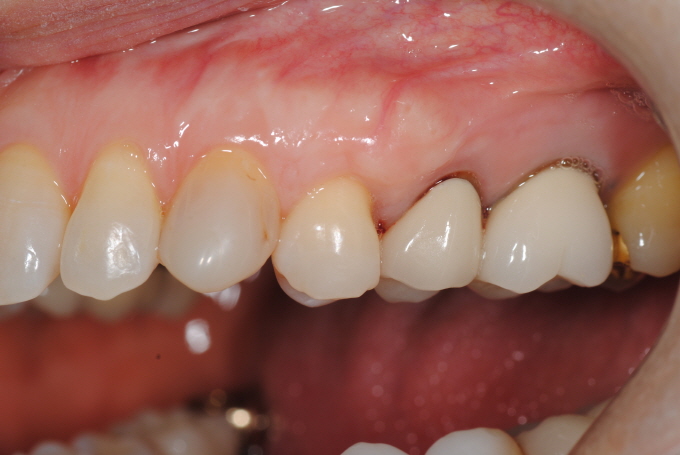

| Fig. 4&5&6: 48¼¼ ¿©ÀÚ, ¿À·£ ½Ã°£À» µé¿©¼ ±³Á¤Ä¡·á¿Í º¸Ã¶Ä¡·á¸¦ ÀüºÎ ¸¶Ãưí, ³²¾ÆÀÖ´ø Marginal migration of gum tissue with hypersensitivity ¹®Á¦¸¦ Subepithelial C.T. graft procedures ·Î¼ Àß ÇØ°áÇÒ ¼ö ÀÖ¾ú´Ù. 2016³â 1¿ù¤·ÀÏ ÇϾÇÁÂÃø Á¦ 2 ´ë±¸Ä¡ ¼³Ãø ±×¸®°í »ó¾ÇÁÂÃø Á¦ 1 ¼Ò±¸Ä¡¿¡ ´ëÇÏ¿© MG plastic surgery¸¦ ÇÏ¿´°í, ÀÌ¾î¼ 2¿ù¤·ÀÏ ÇϾÇÀüÄ¡ºÎ |